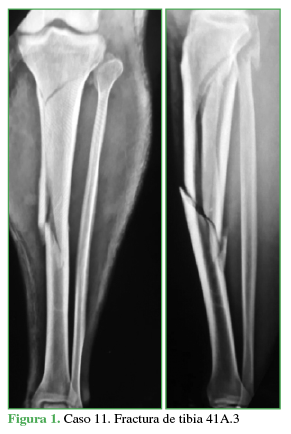

Todos fueron evaluados inicialmente con radiografías simples de frente y de perfil de la pierna, así como con una tomografía computarizada (TC) de la articulación de la rodilla o tobillo, según el extremo de la tibia comprometido (Figura 1). Tres casos eran fracturas expuestas, que fueron tratadas de urgencia, con una limpieza quirúrgica y estabilización inicial con fijador externo. Clasificamos las fracturas expuestas según Gustilo-Anderson9. Los datos demográficos y las características de las fracturas se detallan en la Tabla.

Fractura de tibia 41A

Propia